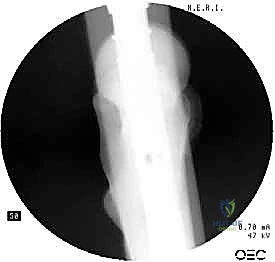

2. الأشعة السينية (X-Rays): هي المعيار الذهبي والأول للتشخيص. يتم أخذ صور من زوايا متعددة (أمامي خلفي وجانبي) لتحديد موقع الكسر، ونوعه، ودرجة تفتت العظام.

3. الأشعة المقطعية (CT Scan): يطلبها الدكتور هطيف في حالات الكسور المعقدة والمتفتتة جداً، حيث توفر صورة ثلاثية الأبعاد تساعد في التخطيط الجراحي الدقيق واختيار حجم المسمار المناسب.

باستخدام جهاز الأشعة السينية المرئية المستمرة (C-Arm Fluoroscopy) داخل غرفة العمليات، يقوم الدكتور هطيف بإعادة العظام المكسورة إلى محاذاتها التشريحية الصحيحة عن طريق الشد والتدوير الخارجي للساق، وكل ذلك يتم مراقبته على الشاشة بدقة متناهية.